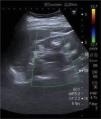

Ultrasound showed kidneys with a chronic appearance, reduced in size, and hyperechoic material in the medulla consistent with nephrocalcinosis (Fig. 1).